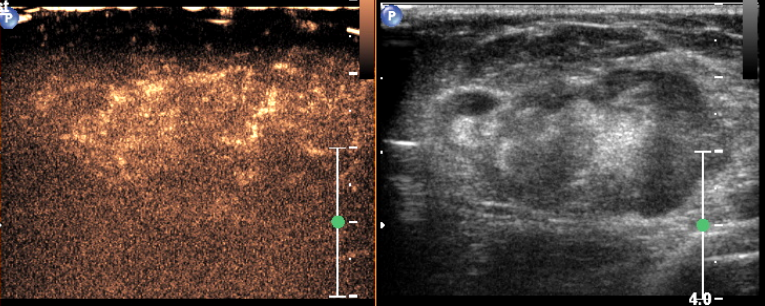

Physical examination revealed a 6.0?×?5.0 cm mass in the left breast. Mammography demonstrated an irregular, fat-containing, heterogeneous mass with circumscribed margins in the upper outer quadrant of left breast. Few scattered foci of coarse calcification were present within the mass. Breast sonography revealed an irregular, parallel, hyperechoic mass with circumscribed margins and no posterior acoustic features in the left breast at 3 o’clock position. Mild vascularity was observed on Color Doppler imaging. Contrast enhanced ultrasound (CEUS) done out of academic interest showed ill-defined, heterogenous enhancing mass, showing irregular shape, having surrounding vessels. Quantitative analysis showed higher PI (pulsatility index), AUC (area under curve) and lower TTP (time to peak) compared to normal tissue. The mass was assessed as Breast Imaging Reporting and Data System category 4b, and ultrasound-guided 14-gauge core biopsy revealed a biphasic tumor composed of bilayered ductal epithelium compressed by the proliferating stroma into leaf like architecture, The stromal cells showed increased cellularity, marked nuclear atypia and pleomorphism with round to oval nuclei, opened up chromatin, prominent nucleoli and moderate to abundant cytoplasm with many bizarre looking tumor giant cells. The stroma showed extensive heterologous lipomatous differentiation composed of neoplastic adipocytes as well as few lipoblasts. Mitosis was 3-4/10/hpf. Final histopathological diagnosis of malignant Phyllodes tumor with liposarcomatous differentiation was given. CT scan chest was done to look for lung metastasis, which revealed an irregular soft tissue mass in left breast with internal focal areas of fat attenuation. No nodules were seen in the lungs. Subsequent lumpectomy was performed and the gross specimen showed a well-demarcated tumor, measuring?6.8?×?6.5 × 3 cm. There were considerable bright yellow fatty components and some cleft-like spaces. Microscopically, the tumor exhibited a typical leaf-like growth pattern with extensive stromal overgrowth and stromal hypercellularity. Extensive areas of lipomatous differentiation were seen ranging from mature adipocytes to lipoblasts showing marked stromal atypia and irregularity. Mitotc activity was 7-8/10hpf. IHC for MDM2 was negative. Overall features were of malignant phyllodes tumor with well differentiated liposarcomatous differentiation.